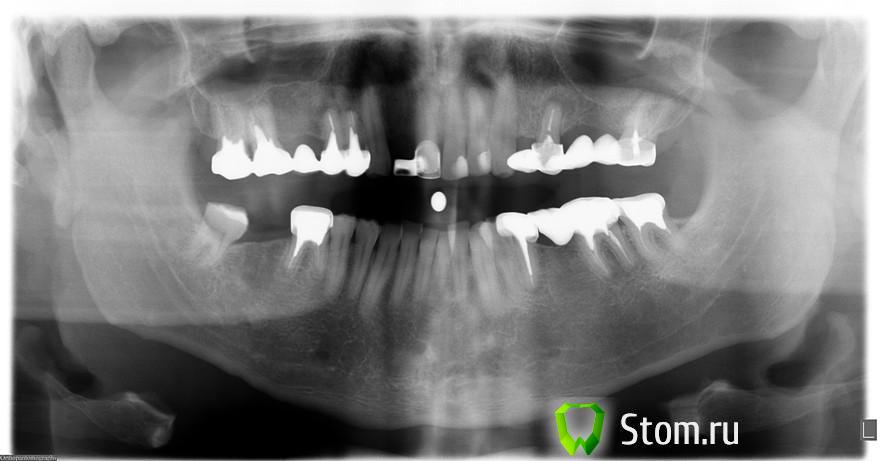

Эндж Опубликовано 20 января, 2012 Поделиться Опубликовано 20 января, 2012 (изменено) Добрый день! Это ортопантограмма моего мужа. Сейчас ему снимают все мосты, перелечивают каналы. На место всех отсутствующих зубов, через две недели доктор собирается одновременно поставить импланты-7 штук. У меня два вопроса:1) Достаточно ли у него костной ткани, почему-то мне кажется, что вверху ее явно не хватает.2) Не слишком ли травматична такая одновременная установка, может лучше разбить хотя бы на два этапа? Изменено 20 января, 2012 пользователем Эндж Ссылка на комментарий

Bier Опубликовано 20 января, 2012 Поделиться Опубликовано 20 января, 2012 наверху слева потребуется синуслифтинг. Если он в планах - то все ок. лучше делать хирургию за раз. чтобы отмучился и все. и антибиотики 1 раз только пить. Ссылка на комментарий

Bier Опубликовано 21 января, 2012 Поделиться Опубликовано 21 января, 2012 на 5-6 зубах слева вверху.В вашем случае как раз таки показана одномоментная с синуслифтингом имплантация. Ссылка на комментарий